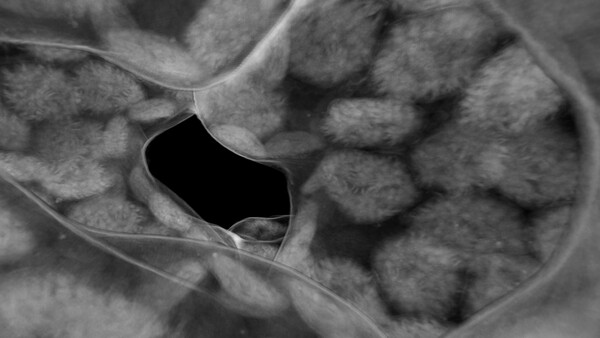

Step into massive 3D images made up of billions of voxels and explore the internal structures of real objects, from animals and human organs to complex materials and devices.